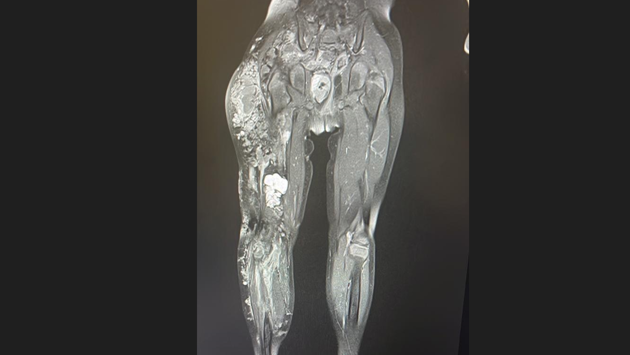

В Кузбассе ребенку удалось поставить диагноз, который зафиксирован примерно у тысячи людей во всем мире. Это сосудистая дисплазия Клиппеля-Треноне-Вебера.

Чтобы выявить эту врожденную болезнь, потребовалось провести сложнейшее исследование с помощью МРТ-аппарата. Диагностику провели в детской больнице имени Атаманова в Кемерове.

– Сложность была в том, что сосудистая аномалия распространялась из полости малого таза на протяжении всей нижней конечности до стопы, – сообщили представители Миндзрава Кузбасса.